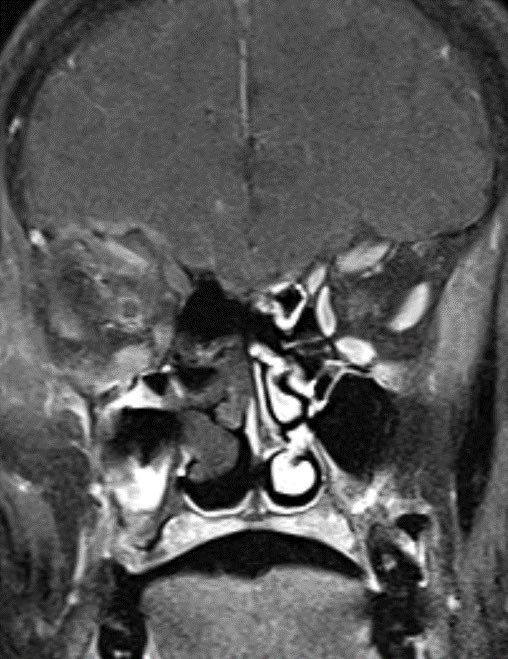

60 y/o with history of diabetes presents with progressive right proptosis, vision loss and confusion. What is the most likely diagnosis? 🧠

💡 Black Turbinate Sign has been reported as a finding highly suggestive of invasive fungal rhinosinusitis in immunocompromised patients

💡 Absent sinus mucosal enhancement is a 🔑 imaging feature as it implies invasion with vascular compromise and necrosis of the mucosa

The black turbinate sign is very specific in the appropriate setting though often not seen

💡 We must look for extra sinus invasion, particular intracranially, intraorbital, retromaxillary and other areas of absent mucosal enhancement to aid in the diagnosis